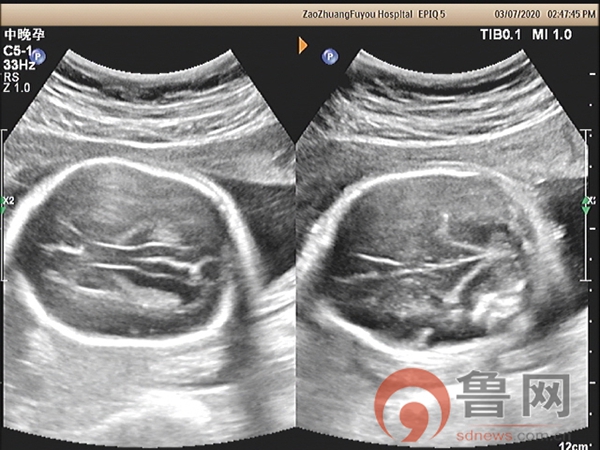

图1:柠檬头,香蕉小脑并后颅窝消失

该孕妇在18孕周唐筛提示神经管缺陷高风险,又进行了无创DNA检查未见染色体异常,18孕周时外院超声检查未发现明显异常,26孕周+时外院因胎儿“小脑显示异常”转枣庄市妇幼保健院超声科会诊。超声检查显示胎儿头颅呈“柠檬头”状,小脑呈“香蕉状”并后颅窝池消失,枣庄市妇幼保健院具有丰富产前超声筛查经验的超声科专家马上意识到,此例胎儿的头部与小脑形态异常,是“开放性脊柱裂”胎儿头部异常的伴发征象。遵循这个思路,随后仔细扫查胎儿脊椎骨,发现脊髓圆锥位置低于腰4以下,骶尾部皮肤回声中断,胎儿脊柱椎体排列尚规则,脊柱无侧弯,无后凸,做出了“开放性脊柱裂”的最终诊断。该例胎儿脊柱的超声异常征象表现细微,远远不如间接征象表现明显,对于经验不足的年轻超声医师极其容易漏诊,因此对本病例诊断过程提出以下思考: